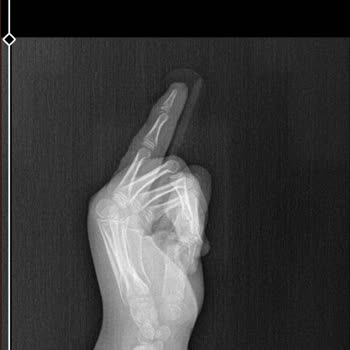

Baltalimanı Kemik Hastanesi Ortopedi bölümünde annemin yaşadığı mağduriyeti paylaşmak istiyorum. Annemin eli kırıldığı için 24 Nisan Cuma günü saat 16.00 civarında acil servise başvurduk, acilde ilk müdahale yapıldı ve ameliyat olması gerektiği söylendi. Bunun üzerine 27 Nisan Pazartesi günü tekrar ...